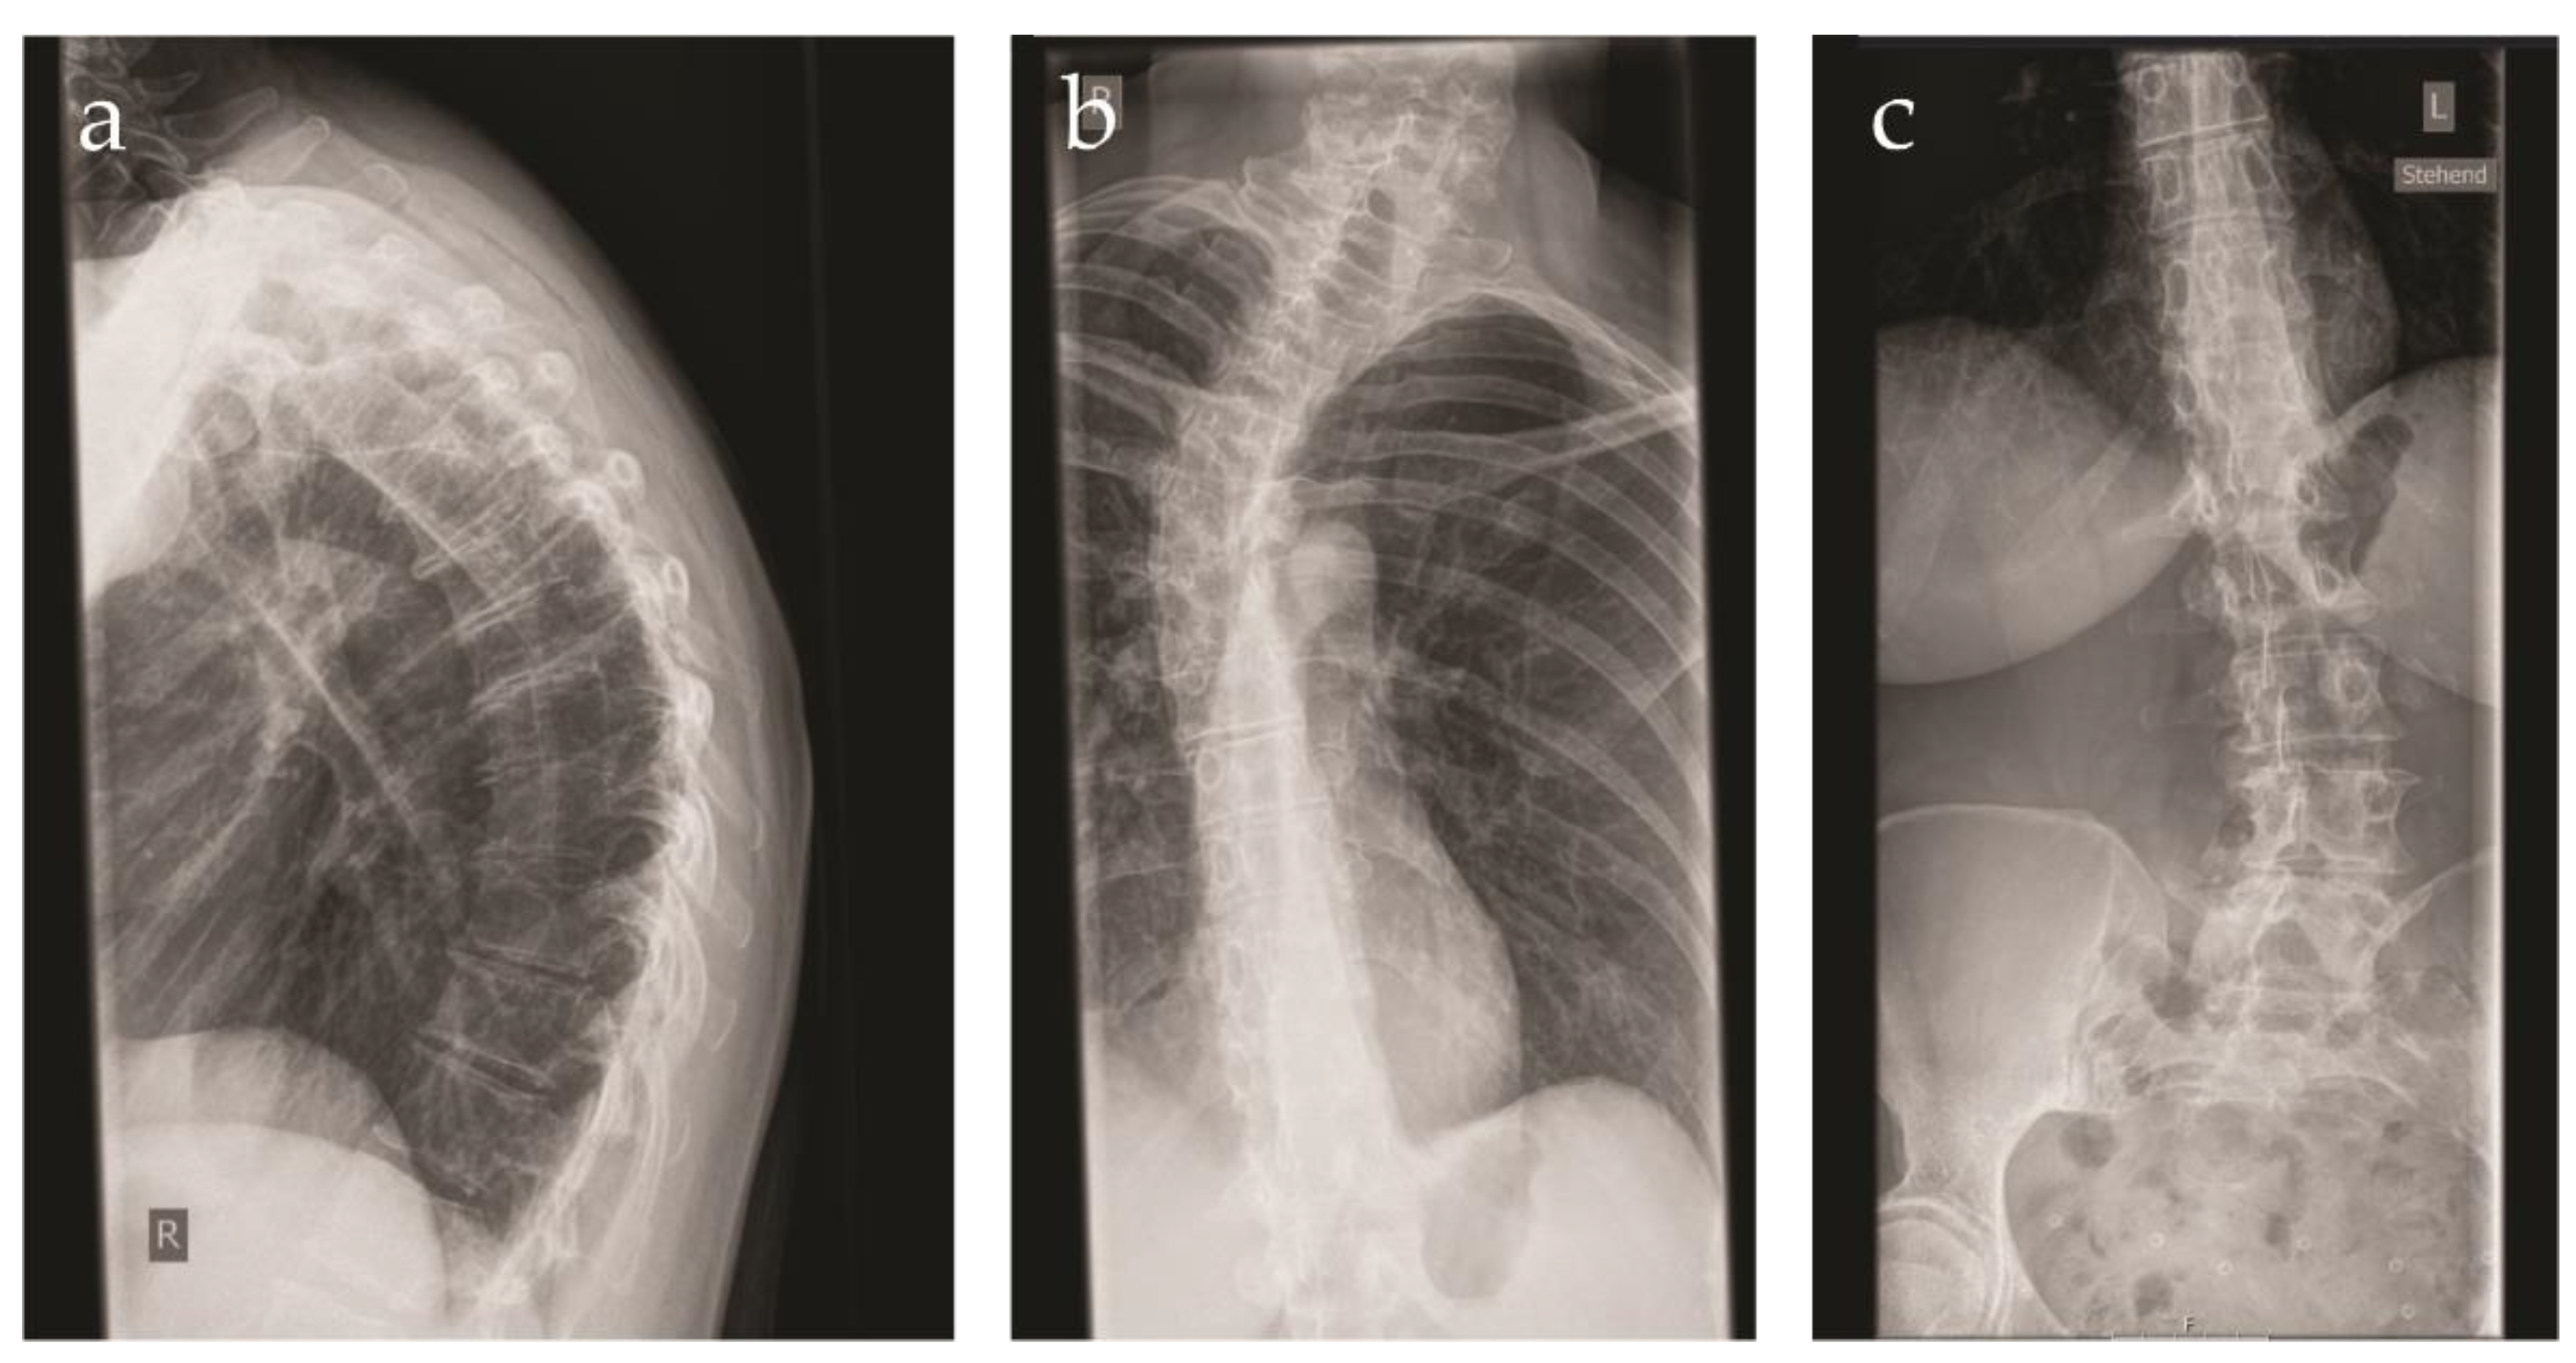

The patient was referred to our center at the age of 41 years because of a suspected connective tissue disorder. She was the first child of consanguineous parents of Swiss origin. The family history was unremarkable. The patient displayed a congenital dislocation of the left hip. Due to recurrent dislocations, an arthrodesis was performed at the age of 2 years. Immediately after surgery, a fracture of the left femur occurred, requiring osteosynthesis. Over the years, multiple joint dislocations ensued, mainly of the shoulders. During childhood, the patient developed a progressive kyphoscoliosis, which was left untreated. At present, the patient displays a right sided gibbus deformity (Figure 1). Upon radiography of the spine, a Cobb angle of 22, 38 and 15 degrees was measured at the cervical, thoracic and lumbar level, respectively.

Figure 1. X-ray images of the vertebral column of the patient at the age of 41 years. (a) Side view demonstrating the pronounced kyphosis; (b) close-up of the pronounced cervical and thoracic scoliosis; (c) close-up of the lumbar scoliosis.